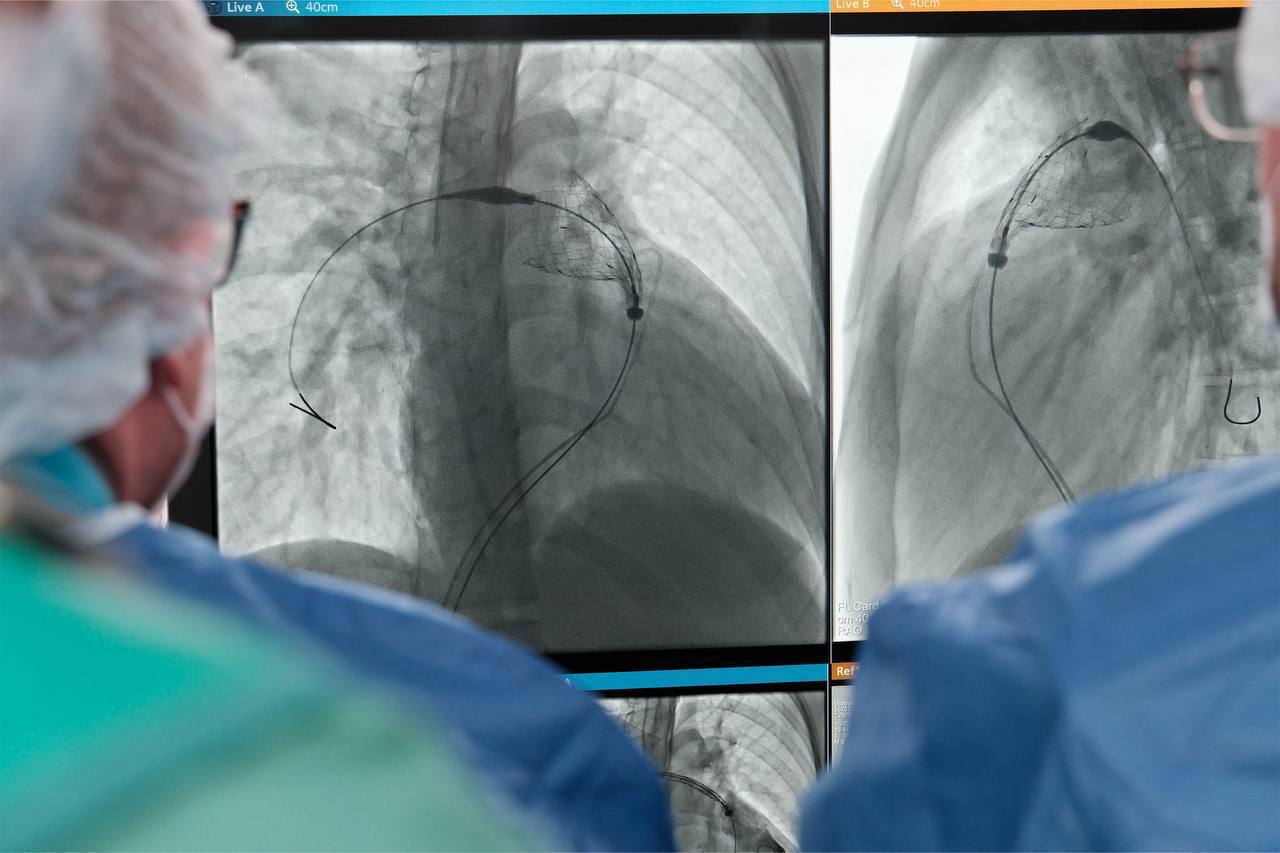

В Детском научно-клиническом центре имени Льва Рошаля провели первые в Подмосковье эндоваскулярные операции по замене клапана легочной артерии подросткам с врожденными пороками сердца.

Семнадцатилетнему юноше с аортальным стенозом и девушке с тетрадой Фалло установили разные типы клапанов — баллонорасширяемый и саморасширяющийся. Операции прошли через прокол бедренной вены, без открытого вмешательства.

По словам заведующего отделением Михаила Комиссарова, метод позволяет избежать больших разрезов и сократить восстановление. Пациенты уже чувствуют себя хорошо и готовятся к выписке.